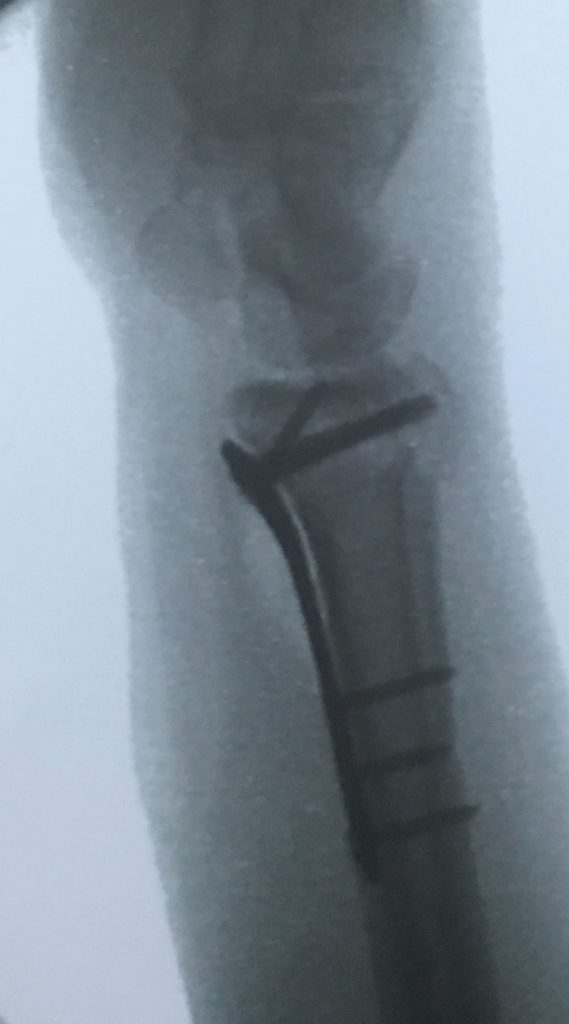

Tras la cirugia en que redujimos la fractura y fijamos los fragmentos con una placa y tornillos podemos ver la restauración de la superficie articular mejorando enormemente el futuro desarrollo de esa articulación con una disminución muy importante del riesgo de artrosis temprana.